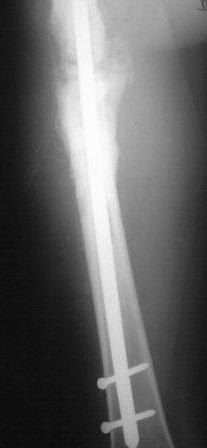

Представляю контрольные послеоперационные рентгенограммы. Во время операции была выделена зона перелома небольшим разрезом, произведена декортикация. Окончательный остеосинтез.